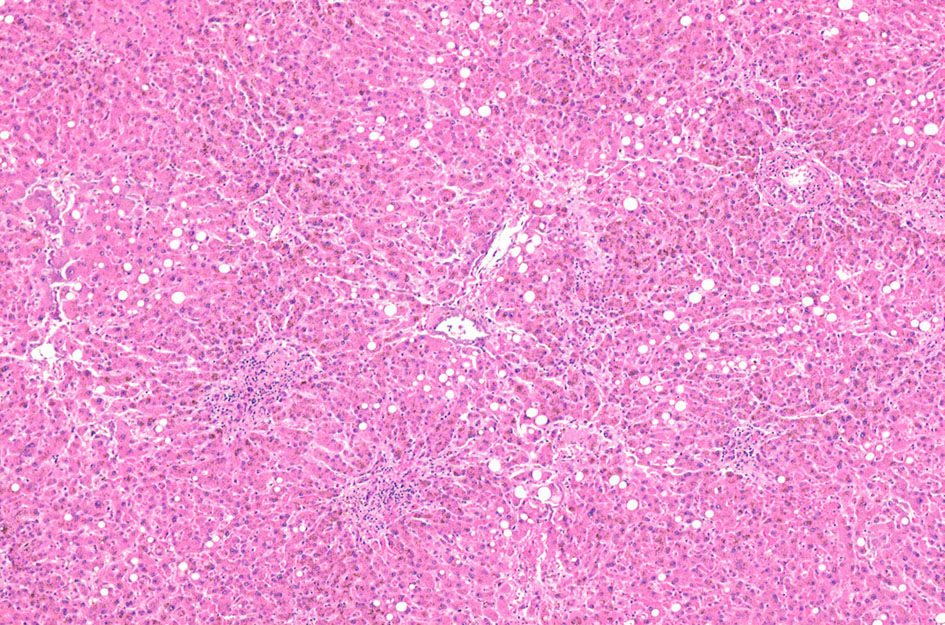

IWT症例 70歳代男性 3年前より胸部不快感, 体重減少。大球性正色素性貧血を指摘される。

骨髄クロット標本

70歳代男性の骨髄。hypercellular marrow. M/E=1-2, erythropoietic hyperplasiaを認める(1, 2). megaloblastosisが出現。(3).

Mgkは成熟大型のものが多い(4). 単核, 小型球状核のMgkも認められる(5)

CD42b染色によるMgkでは大型がほとんどでmicromegakaryocytesは増加していない。